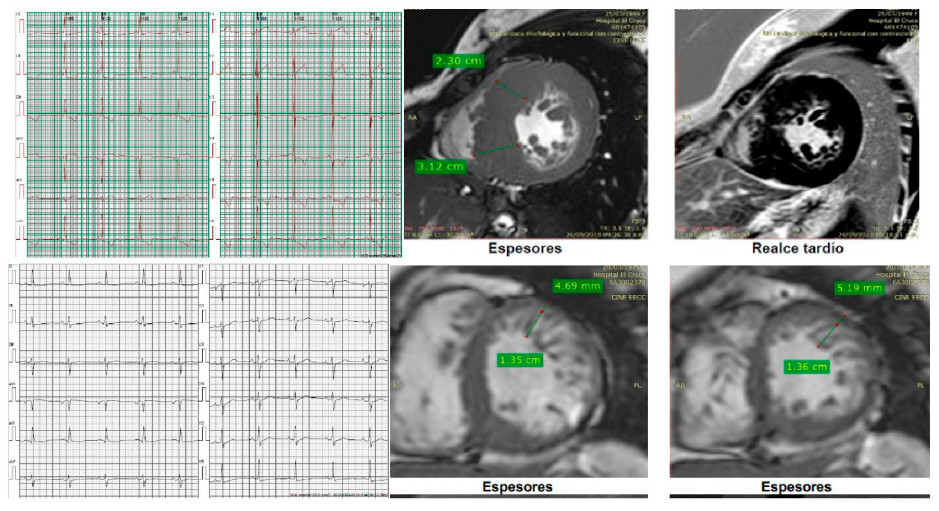

El caso índice es una mujer con hipertrofia severa diagnosticada a los 37 años, con implante de CDI por taquicardia ventricular (TV) monomorfa sostenida sincopal a los 47 años. La CRM que evidenció Miocardio no compacto (MNC) y G+ (MYH7: c.1208G>A (p. Arg403Gln). Sus 3 hijos presentan G+, dos de ellos con F+, ECG patológico (hipertrofia ventricular izquierda y ondas T negativas en la cara anterolateral) ECG y CRM de uno de sus hijos arriba y de la paciente abajo.